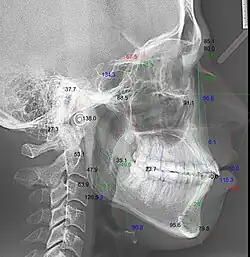

Телерентгенография с кефалометрическим анализом

Кефалометрия, или кефалометрический анализ, — геометрическая абстракция, созданная ортодонтами и челюстно-лицевыми хирургами для дифференциации нормы от патологии посредством тригонометрических функций[1][2].

Кефалограмма — геометрическая обрисовка телерентгенограммы для изучения абстрактных закономерностей — угловых и линейных кефалометрических параметров[3][4].